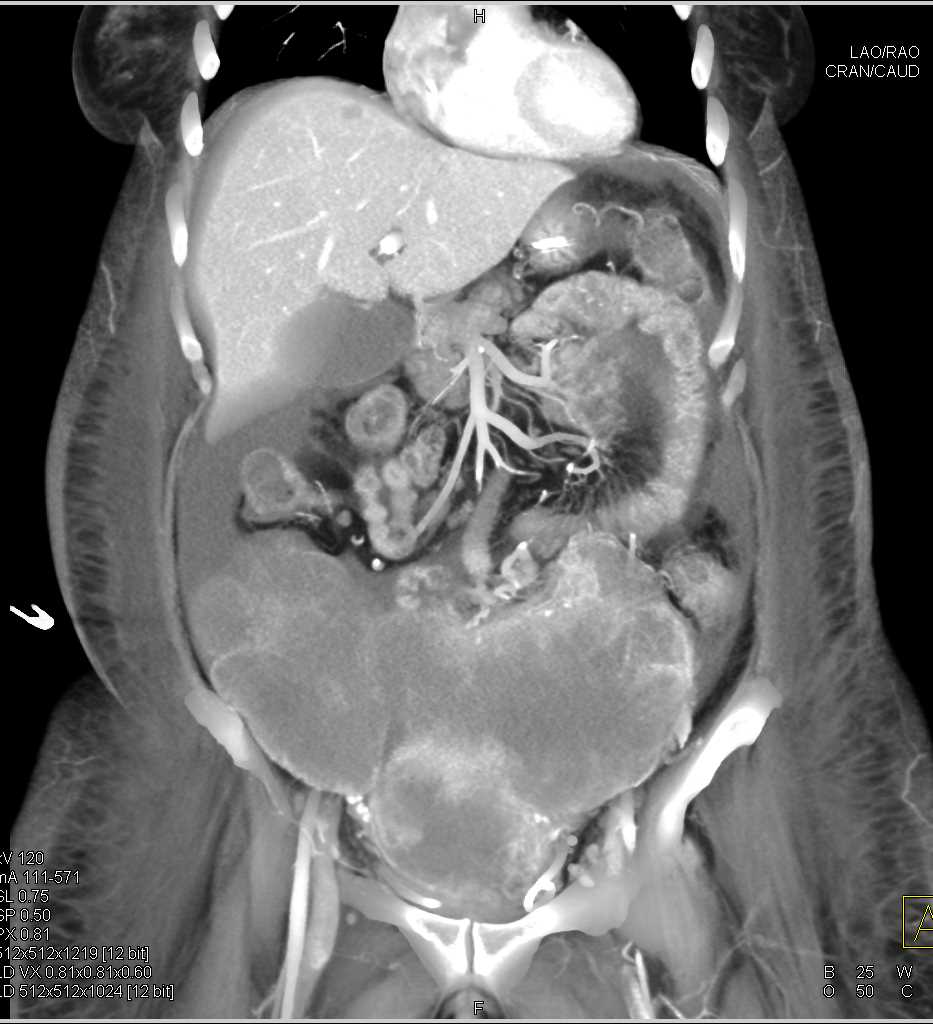

Ovarian Cancer with Carcinomatosis